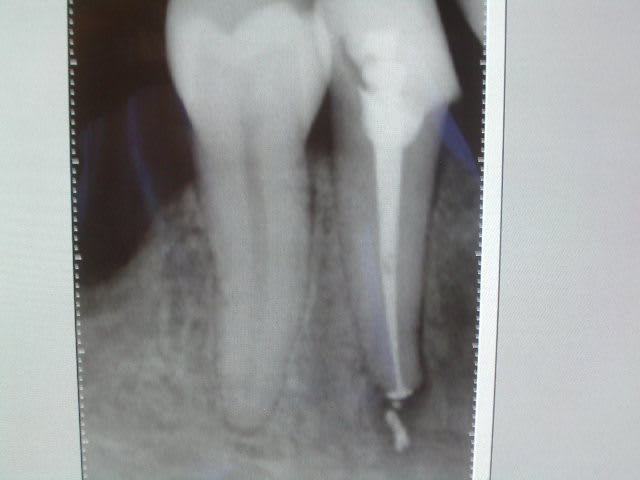

exemple, 47 serait tellement bien en pilier de bridge.

( sauf si on fait de l'implanto, car à ce moment la, on ne se pose même plus la question de savoir si c'est sauvable )( que personne ne se sente visé ! :-))

Radio1 cqvbeu - Eugenol

Oups, un coup de lentulo un peu trop généreux ( mais c'est n'est pas trop grave, c'est pas du N2 ! ).

Et en plus ce n'est même pas conforme aux données de la science ! ouh !

Radio2 dtynqn - Eugenol

J'ai voulu sauver une dent et je me suis fait chier une heure, alors que cela aurait pris 5 mn à Alhoun, sans risque de dépassement.

La question que m'inspire ce cas est la suivante : la reprise a été faite sous digue, irriguée tout comme il faut, radio lime en place, localisateur.

Tout ce travail gaché ( pour l'instant ) parce que j'ai conservé la technique d'obturation que l'on m'a enseignée il y a 15 ans.

Je sais qu'il faudrait que je change de technique, et pourtant, le temps passe, et je reste au bon vieux lentulo en me disant : " il faudrait ... )